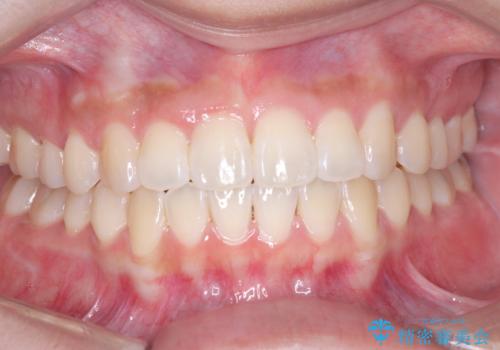

翼状捻転と叢生を矯正で改善

- 患者様は、上の前歯に翼状捻転(歯が回転して生えている状態)があり、全体の歯並び(叢生)の改善を希望して来院されました。診断の結果、非抜歯での治療が可能であると判断し、上顎にリンガルアーチを装着し、矯正用アンカースクリューを併用することで臼歯部を確実に遠心移動させる治療計画を立案しました。これにより、スペースを確保しつつ、前歯をきれいに並べることを目指しました。

治療では、審美ワイヤーを使用し、目立ちにくく配慮しながら矯正を進めました。上顎にリンガルアーチと矯正用アンカースクリューを用いて臼歯部を安定的に遠心移動させ、歯列全体のスペースを確保しました。その後、回転していた前歯を正しい位置に配列し、全体的な歯並びの改善を行いました。治療中は、装置の適切な管理と口腔衛生を徹底することが重要でした。結果として、見た目だけでなく機能的にも優れた歯列を実現することができ、患者様にもご満足いただけました。